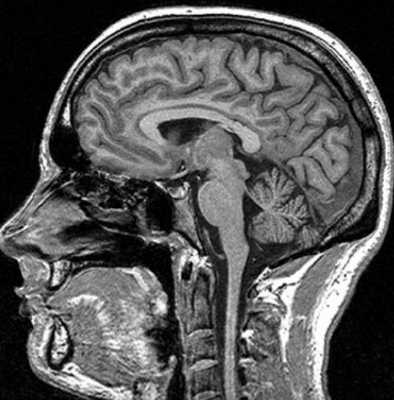

Магнитно-резонансная томография базируется на способности магнитного поля изменять состояние атомов водорода в молекулах воды. Процедура информативна относительно мягких тканей, насыщенных жидкостью. Структуры организма с низким содержанием воды на снимках отражаются плохо. МР-томограф фактически «не видит» костную ткань. По этой причине рутинная диагностика переломов включает рентгенографию и КТ (в экстренных, спорных либо сложных ситуациях). При травмах головы стандартное обследование с помощью Х-лучей нередко сочетают с магнитно-резонансной томографией. В зависимости от того, что показывает МРТ костей черепа, дополняют тактику лечения, основанную на результатах КТ. Процедура дает информацию о состоянии мягких структур и влиянии на последние травм.

Показывает ли МРТ перелом черепа?

Диагностическая ценность магнитно-резонансной томографии высока при травмах сложных структур организма (черепная коробка, позвоночник, сочленения). По результатам сканирования диагностируют не сам перелом, а сопутствующие повреждения (разрывы связок, мышц, компрессию тканей и пр.).

На вопрос «Показывает ли МРТ перелом черепа?», врачи дают отрицательный ответ. При травмах головы методом выбора является компьютерная томография. По снимкам оценивают состояние костей, обнаруживают малейшие повреждения последних, кровотечения. Компьютерная томография особенно информативна в первые 48 часов после получения травмы. В дальнейшем изменения в мозге контролируют посредством МР-сканирования.